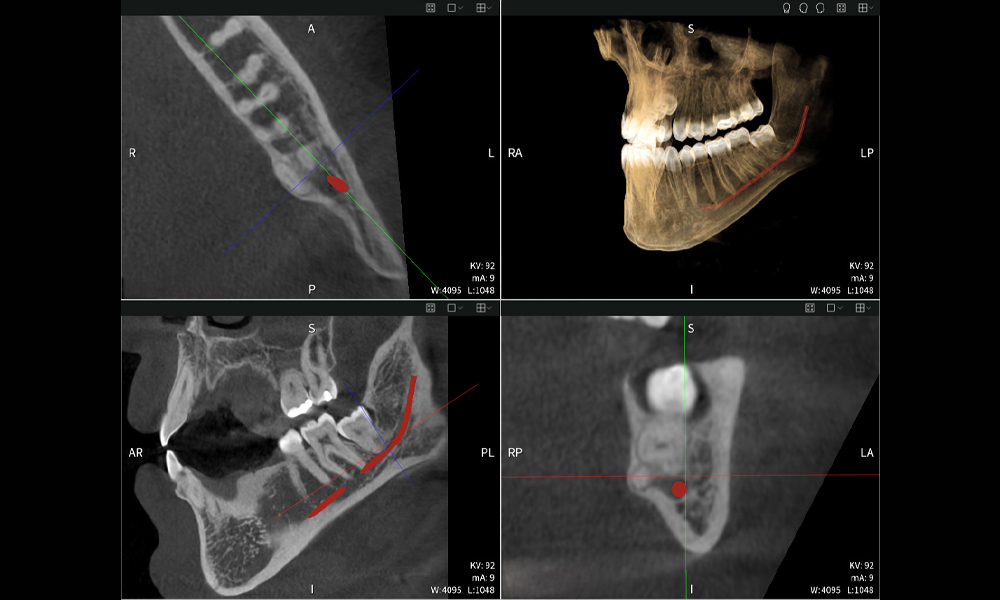

Abbildungen b–d zeigen verschiedene Ansichten einer 3D-Rekonstruktion des Unterkiefers und bieten eine umfassende Übersicht über die Anatomie des Unterkiefers, die Lage der Nerven im Verhältnis zu den Zähnen und ermöglichen die Beurteilung der Zahnsymmetrie und Ausrichtung.

Abbildung d zeigt den bereits vorbehandelte Zahn 48, dessen Krone entfernt wurde und dessen Wurzeln nahe am Nerv belassen wurden, was das hohe Risiko einer Nervenschädigung verdeutlicht.